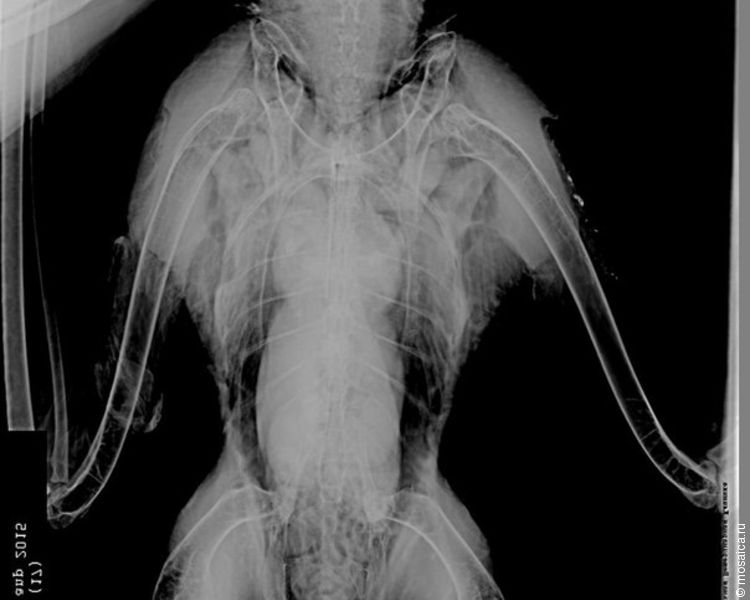

- Но даже в домашних условиях ему холодно, поэтому дополнительно включаем обогреватель. Сделали снимок легких. Выявлен токсический отек верхушечных долей легких, токсический гастроэнтерит, гепатит и нефрит. Его периодически подташнивает, с калом идет практически один мазут. К, сожалению, статистика выживания птиц, пострадавших от нефтепродуктов, весьма плачевная, - сообщили в центре спасения диких птиц. - Очень надеемся, что птица переживет первый критический период отравления 7 дней и потом пойдет на поправку.

Фото заповедника «Нижняя Кама», Центра спасения диких птиц